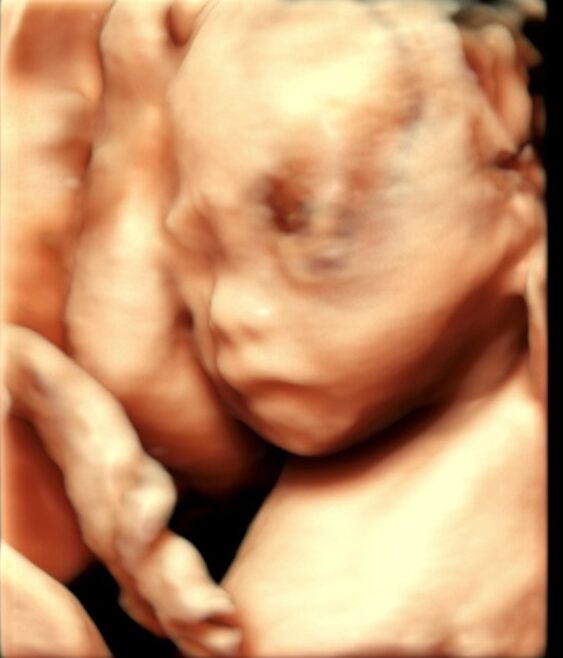

条件が良ければ、こんな感じで赤ちゃんをみることができます(写真は、お母さんにホームページに載せることを許可していただいています)。

赤ちゃんの協力も必要なので、残念ながらいつもこのようにみえるわけではありまんが、

お腹の中で元気に育っている姿をみると、幸せのおすそ分けをしてもらっているような気分になります。

飲んだり、呼吸したり、体を動かしたり、産まれたあとにしっかりと生きていくために頑張って練習しています。